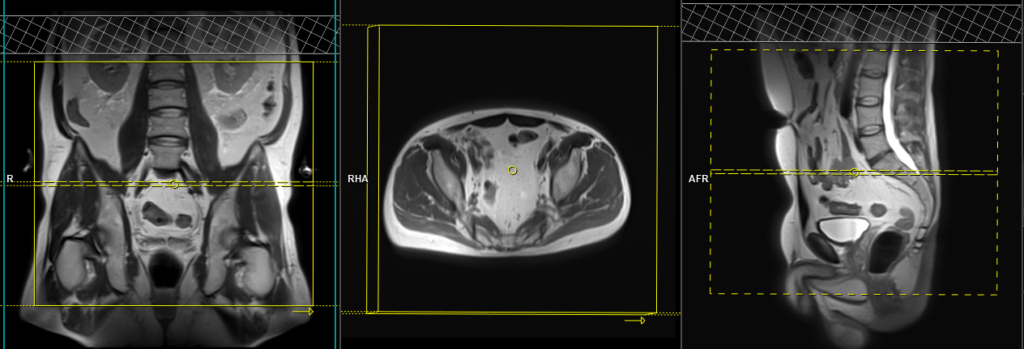

T1 TWIST DIXON\T1 VIBE 3D fat sat axial dynamic 4 pre 22 post

Plan the axial TWIST 3D block on the sagittal plane; angle the positioning block horizontally across the prostate (i.e., parallel to the base of the penis). Check the positioning block in the other two planes. An appropriate angle must be given in the coronal plane (parallel to the right and left femoral heads). Slices must be sufficient to cover the whole prostate and seminal vesicles. Additionally, to minimize artefacts arising from arterial pulsation, peristalsis, and breathing, consider incorporating saturation bands on top and in front of the axial block. Ensure an adequate amount of slices and phase oversampling are utilized to prevent wrap-around artifacts.

A dynamic TWIST VIBE DIXON dynamic sequence consists of 26 3mm 3D scans. Contrast injection must be administered after the fourth dynamic sequence.

Parameters TWIST DIXON

TR 4-5 | TE 1.25 2.49 | FLIP 14 | NEX 1 | SLICE 3MM | MATRIX 204X192 | FOV 180-200 | PHASE R>L | DYNAMIC 26 SCAN | IPAT ON |

Parameters FLASH 3D

TR 4-5 | TE 2 | FLIP 12 | NEX 1 | SLICE 3MM | MATRIX 256X192 | FOV 180-200 | PHASE A>P | DYNAMIC 11 SCAN | IPAT ON |